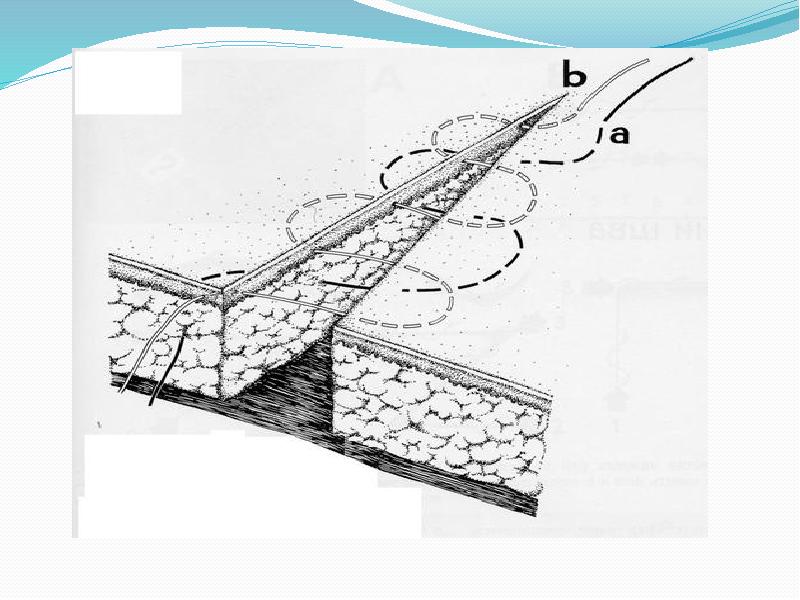

- 53. Двухрядный непрерывный шов Глубокие раны могут быть закрыты двухрядными непрерывными швами.